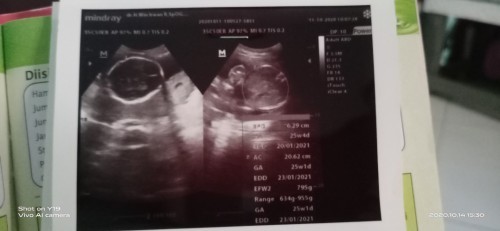

23 th usia kandungan 25w5d menurut hasil usg Minggu kemarin.tp kalo hitungan terakhir haid 30minggu ...ntah yg bnr yg mana Bun,sy juga bingung ,π€π€